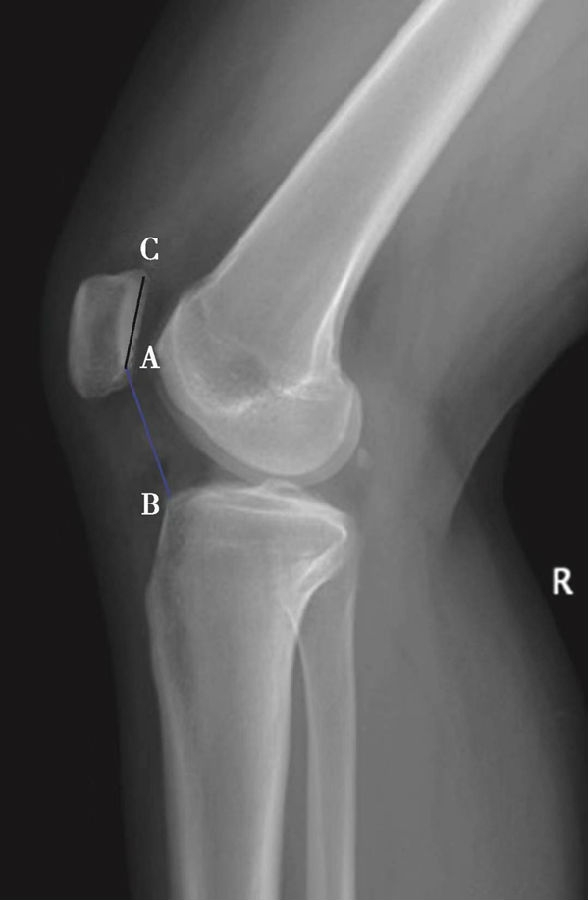

如图示:AB是髌韧带长度,AC髌骨纵轴长度。Insall-Salvati指数=AB/AC(图4)。

图4 Insall-Salvati指数 =AB/AC=1.10,为正常髌骨高度

但是此法测量髌骨韧带时往往依赖准确的估计胫骨结节与髌骨下极的位置。因此,髌骨下极和胫骨结节的病变都会影响测量的结果,尤其是发生胫骨结节骨软骨炎的患者确定这一位置便更加的困难。此外,该指数不能用于评估胫骨结节向近端或远端移位的效果。因为该指数测量所使用的标记在胫骨结节术后均未发生改变,Insall指数也就不会变化。